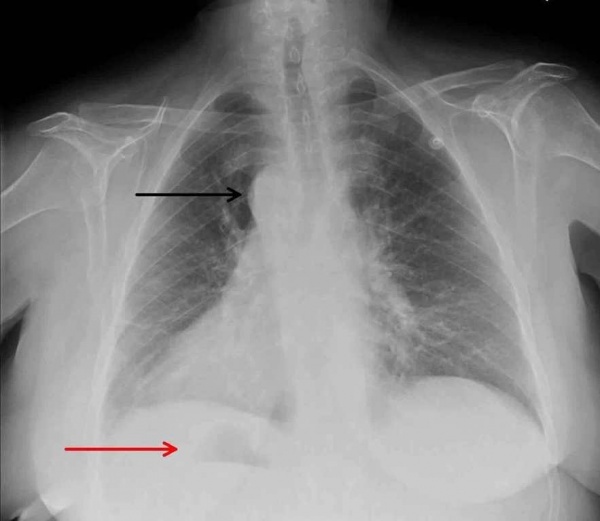

- Рентгенография ОГК. На рентгенограмме визуализируется смещение сердечной тени вправо, при комбинированных аномалиях изменяются контуры магистральных сосудов. Чтобы подтвердить транспозицию проводится рентгенография органов брюшной полости.

Рентгенография ОГП. Декстрокардия: дуга аорты (черная стрелка), правый желудочек (красная стрелка).